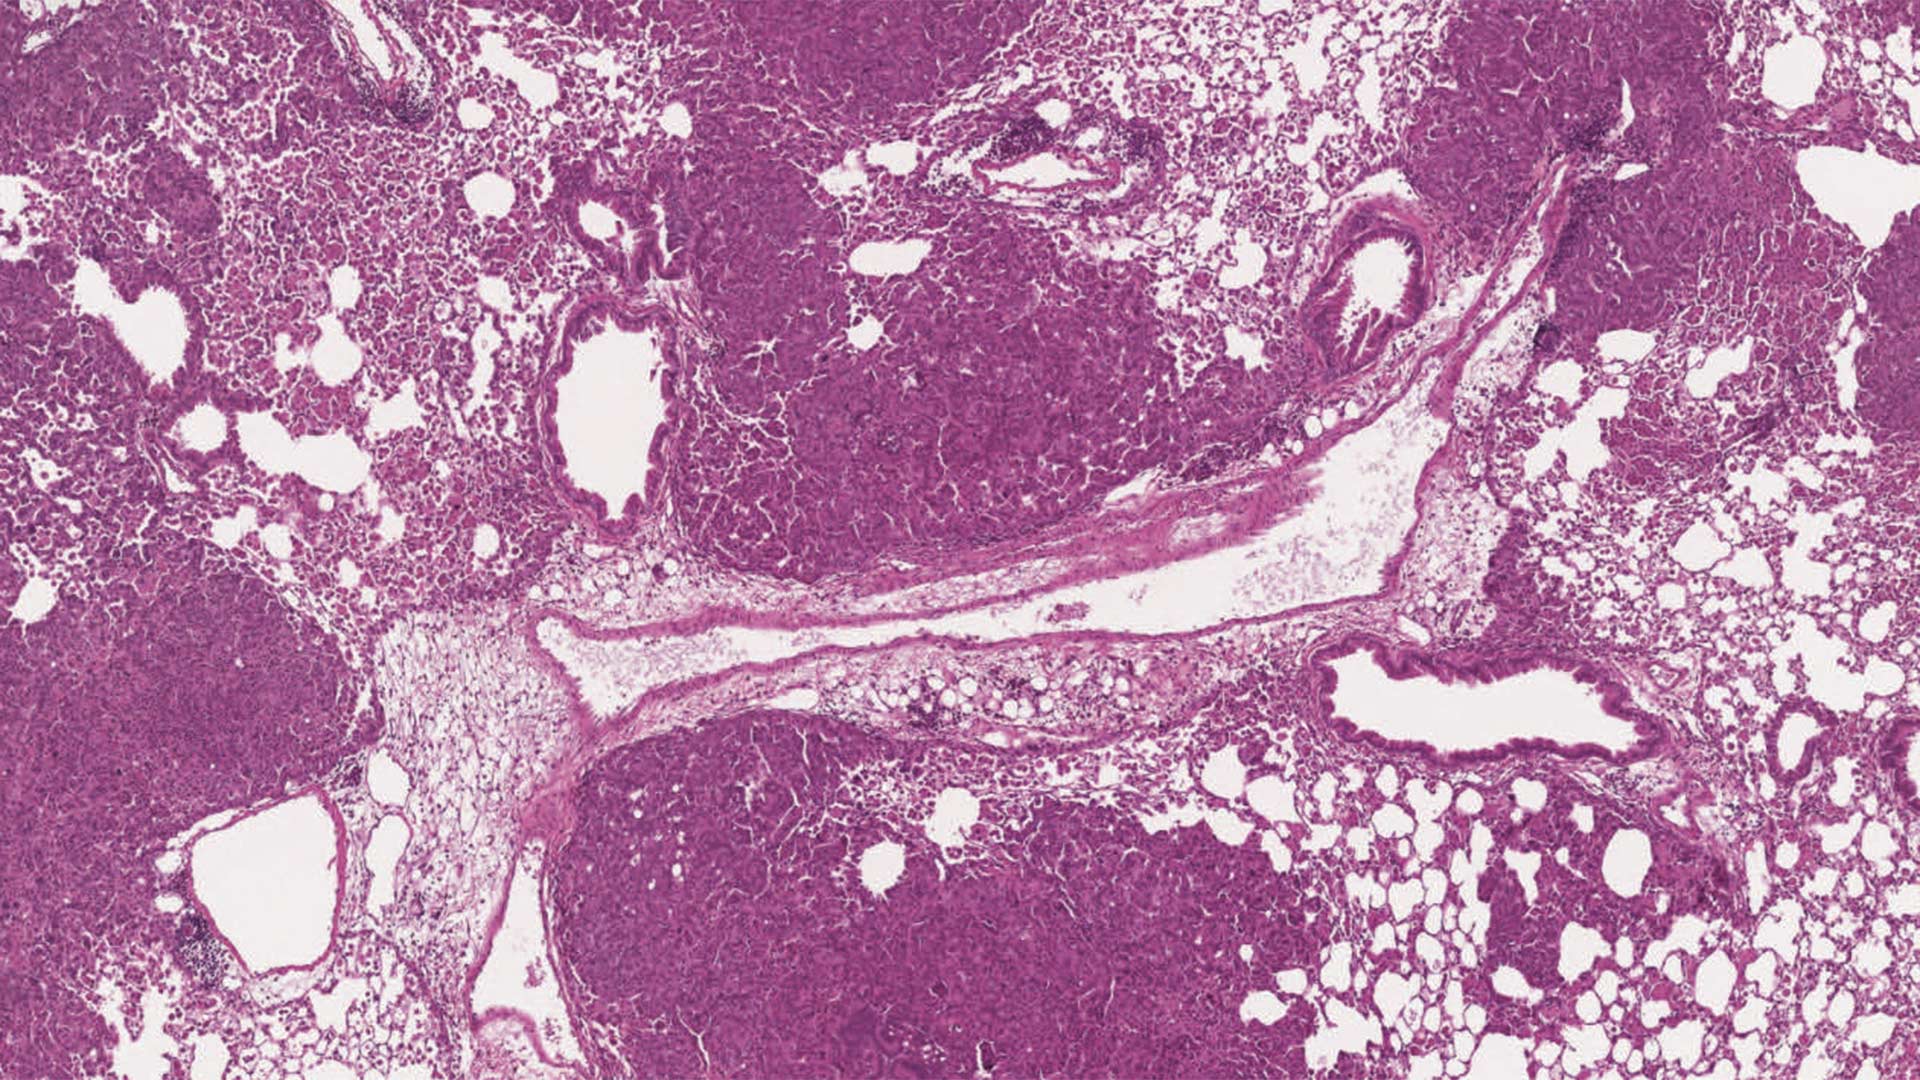

As a postdoc at the Massachusetts Institute of Technology, Westcott and his colleagues created new mouse models to study differing responses to immunotherapy in colon and lung cancers from MMRd. The models had more mutations across their genomes to more accurately reflect tumors seen in human patients.

Westcott had a hypothesis. Although the tumors had many mutations, maybe they were too different from cell to cell to trigger an immune response. To test it out, the team isolated tumors with identical mutations in all cells, or clonal mutations, and tumors with identical mutations in only some cells, or subclonal tumors. They found that mice with clonal mutations responded to immunotherapy. Those with subclonal mutations did not.